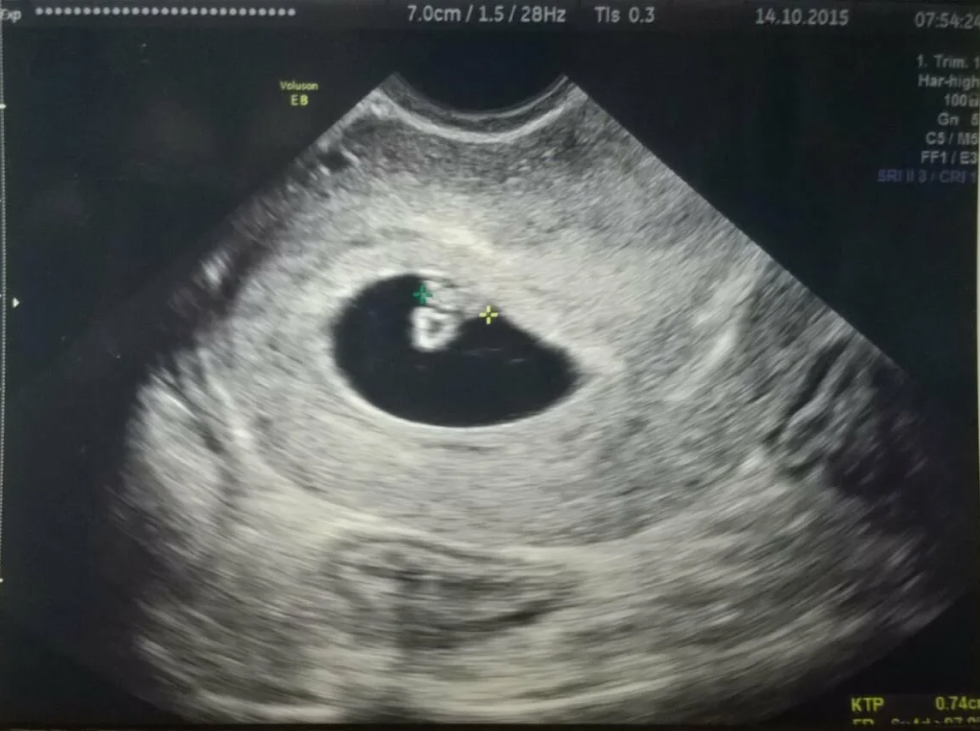

🔸 УЗИ на шестой неделе

На шестой неделе беременности УЗИ может подтвердить наличие беременности и помочь оценить развитие плода. Этот метод позволяет определить размер малыша, место прикрепления в матке и маточный тонус. Более того, на УЗИ можно увидеть сердцебиение вашего крошечного, но уже любимого малыша. Если вы испытываете неприятные ощущения в животе, УЗИ поможет выяснить, не являются ли они признаком угрозы прерывания беременности.

Несмотря на то, что ультразвук считается безопасным, не стоит делать его многократно без медицинских показаний. Позвольте природному процессу идти своим чередом, ведь каждое развитие беременности имеет свои особенности.